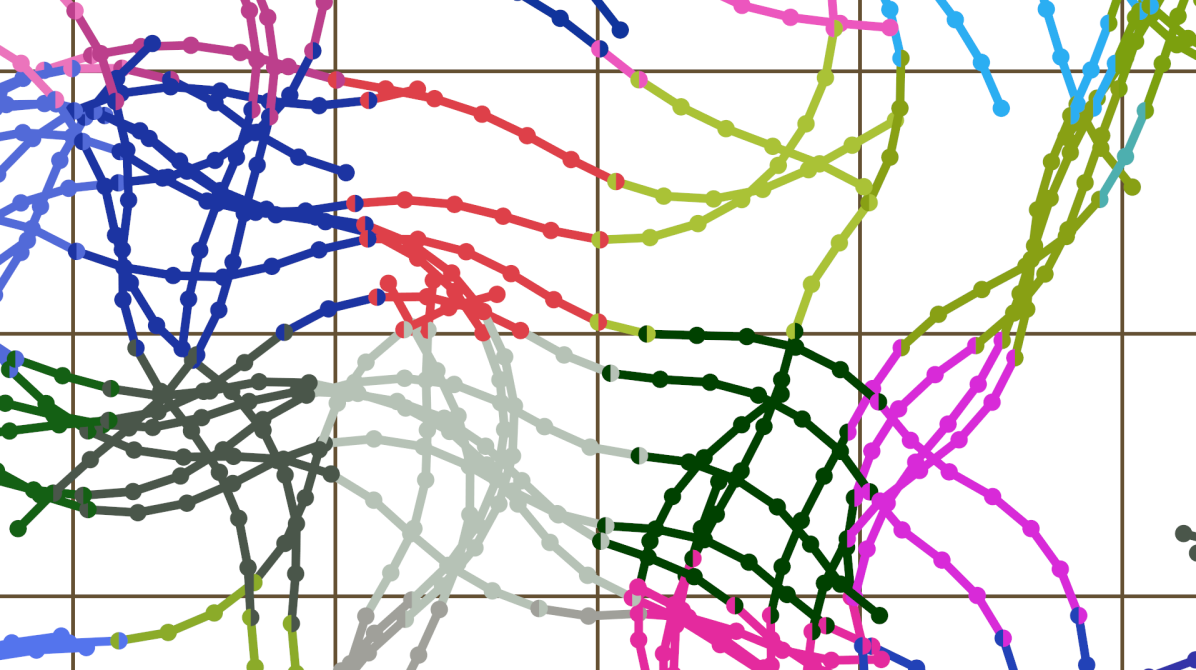

Intuitively, grouping points of a streamline based on which voxel the points fall in, can be seen as dividing the streamline points into several parts when a streamline passes through multiple voxels. This can be seen in Figure 1 where each streamline is split based on the voxel coordinate of each streamline point. In the rest of the paper, we will refer to these parts as ”voxlines”. A voxline is defined as a sequence of consecutive points of a streamline that is bounded by a voxel. In this context, consecutive means that there are no missing points between the minimum and maximum points of a group of streamline points. For example, points with streamline indices would be considered consecutive, while would not.

To generate voxlines making up the streamlines we can split each streamline in voxlines based on the voxel each point falls within. However, using only the points in each voxline would result in gaps between voxels when rendering the voxlines. Consider a streamline that is separated into two voxlines. If we render these voxlines as two distinct sets of lines, there will be a gap between them because no line is drawn between the end of the first voxline and the beginning of the second voxline. So defining the voxlines by using only the points that fall within the voxel would cause lines that cross the voxel borders to not be rendered. To address this issue, when generating the voxlines we add an additional point for every voxline that does not contain the final streamline point. This additional vertex corresponds to the next point in the streamline that falls outside of the voxel. By doing this, we fill all the gaps between the voxlines. This is illustrated in Figure 1 by certain voxlines having an extra point outside of their voxel boundary and are thus part of both voxel meshes.

Algorithm 1 implements the voxelization and voxeline generation described in Sections 2.1 and 2.2. It generates the set of voxlines and groups them based on voxel coordinates by iterating over the streamlines. Each streamline is split into voxlines whenever a point is found with a different voxel coordinate than the previous point. Voxlines that do not contain the final point have an additional point added to ensure proper connectivity between voxlines.